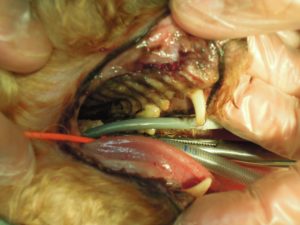

8.左側上顎の歯も全て抜歯し、

9.左側下顎も全て抜歯しました。

顎先が細くやせた状態になっています。